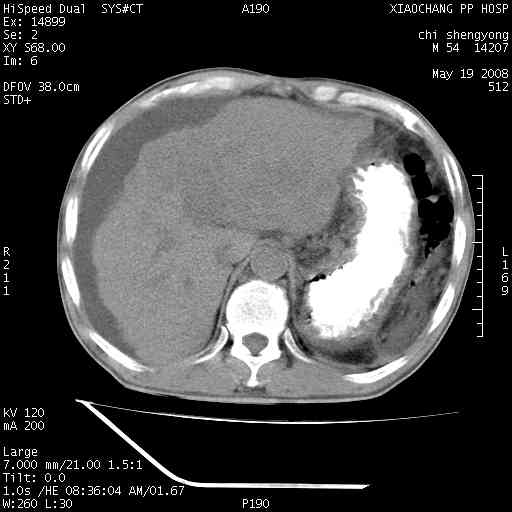

以下是引用zjzjr在2008-5-21 10:52:00的发言:[br]肝左叶巨块型肝癌伴门静脉左支瘤栓形成.肝硬化、腹水,胃底静脉曲张,脾术后改变。

以下是引用随光逐影在2008-5-21 16:20:00的发言:[br]1)肝左叶肝癌伴门静脉左支瘤栓形成,腹膜后淋巴结转移。2)肝硬化、腹水、胃底静脉曲张。3)胆囊炎。4)脾脏缺如,为切除术后所致。